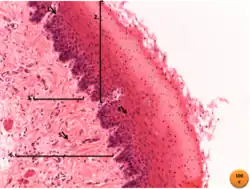

- Capa mucosa: Conformada por el epitelio y el tejido conectivo subyacente. El epitelio#Epitelio estratificado plano no queratinizado tiene varias capas de células y recubre la luz del esófago. Este epitelio está renovándose continuamente por la formación de nuevas células de sus capas basales. Para facilitar la propulsión del alimento hacia el estómago, el epitelio está recubierto por una fina capa de mucus, la cual se forma por las glándulas cardiales y esofágicas. El tejido conectivo es de tipo laxo, y se separa de la siguiente capa (submucosa) por medio de la capa muscularis mucosae.

- Capa submucosa: capa que se encuentra por debajo de la mucosa, y está formada por tejido conectivo denso, se encuentran en ella glándulas esofágicas.

- Capa muscular: está formada por dos capas de músculo liso, una capa interna de células de dirección circular y otra capa externa de células musculares longitudinales, que cuando se contraen forman ondas peristálticas que conducen el bolo alimenticio al estómago.

- La capa muscular es más flexible y las mediciones biomecánicas han demostrado que tiene un módulo de elasticidad menor. Esta diferencia de rigidez/flexibilidad implica que la distribución de esfuerzos en un esófago no puede ser uniforme.

- Capa serosa o adventicia: Formada por tejido conectivo, excepto en la región del receso vertebromediastinico, donde las pleuras lo revisten parcialmente.[4]

Unión esofagogástrica (también unión gastro-esofágica): es la unión entre el esófago y el estómago. A simple vista, el color rosa de la mucosa esofágica contrasta con el rojo más intenso de la mucosa gástrica y la transición entre las dos se puede ver como una línea irregular, que a menudo se denomina «línea z». En la microarquitectura, el examen histológico revela una transición abrupta entre el epitelio#Epitelio estratificado plano no queratinizado también (Epitelio escamoso estratificado) del esófago y el epitelio cilíndrico simple del estómago.